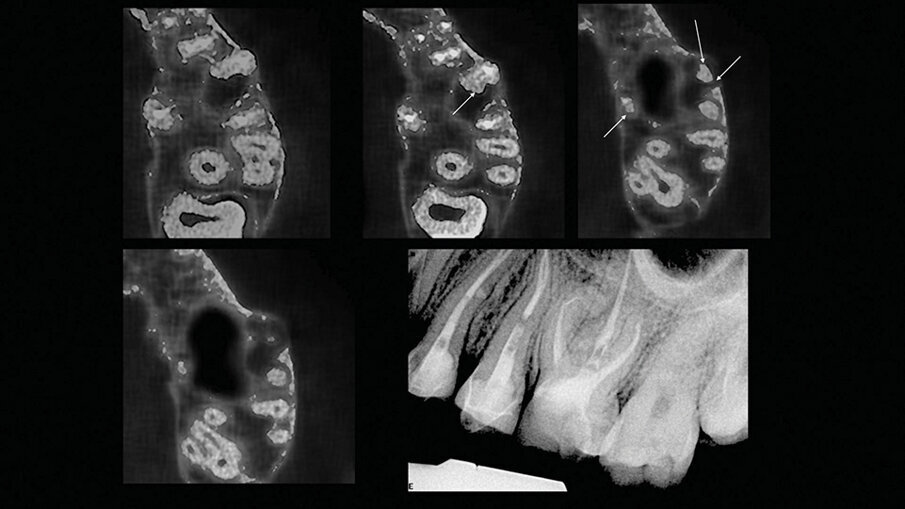

Slučaj 3 – Slika br. 8: Preoperativni CBCT sken